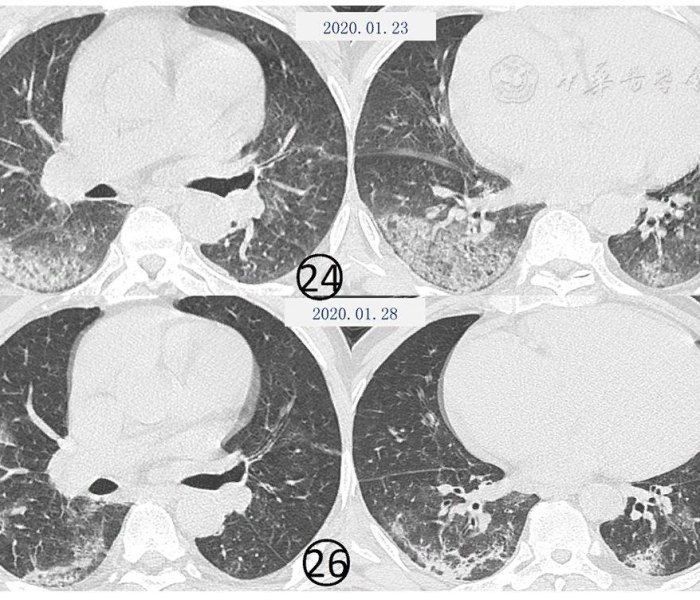

江苏23日新型肺炎/江苏23日新型肺炎最新消息

2020年1月23日,江苏省报告了首例新型冠状病毒肺炎(COVID-19)确诊病例,这一事件标志着该省正式进入疫情防控的紧急状态,作为中国经济和人口大省,江苏的疫情动态牵动着全国神经,本文将从疫情背景...